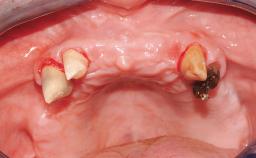

Immediate Loading of Six Implants in the Mandible and Six Implants in the Maxilla and Final Restoration with Full-Arch CAD/CAM Metal Framework FDPs Involving Digital Planning and Guided Surgery

Immediate loading of dental implants is increasingly popular with clinicians and patients. The idea of delivering a restoration directly after implant insertion,combined with a less invasive procedure (flapless protocol), has made treatment protocols involving dental implants more accessible to dentists and patients. However,immediate-loading concepts require sophisticated and exact planning. To facilitate this, conventional panoramic tomographs and periapical radiographs are often taken with the patient wearing a radiographic template simulating the preoperative prosthetic design. However, these radiographs do not provide all the necessary information. In addition, some protocols call for conventional surgical templates fabricated on the diagnostic cast. These will inform the bone drilling points and drill angles, but do not reference the underlying anatomical structures or provide exact 3-D guidance.

Case Type Edentulous Maxilla

Bone Volume Horizontally and vertically sufficient Horizontally deficient Deficient vertically or deficient vertically AND horizontally